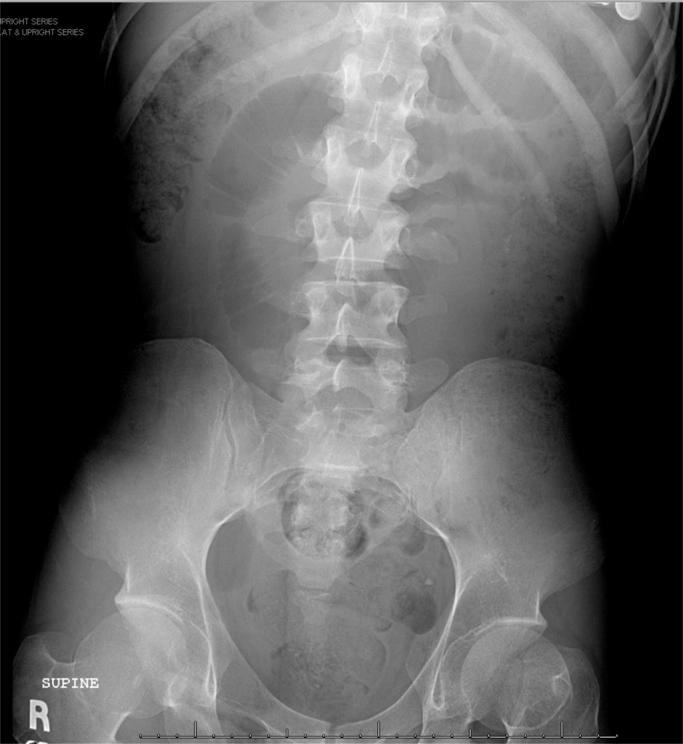

A 28-year-old male with no past surgical history, known to have severe mental retardation presented with anorexia. CT scan demonstrated dilated small bowel loops and intraluminal ileal mass with mottled appearance. At exploratory laparotomy, a bezoar was found impacted in the terminal ileum 5-6 inches away from the ileocecal valve and was removed through an enterotomy.

一名28岁男性,无既往手术史,已知患有严重智力障碍,出现厌食症状。CT扫描显示小肠肠袢扩张,回肠腔内有斑驳状肿物。在剖腹探查术中,发现一枚胃石嵌顿在距回盲瓣5 - 6英寸处的回肠末端,并通过肠切开术将其取出。

Bezoars are concretions of fibers or foreign bodies in the alimentary tract. Small bowel obstruction is one of common clinical symptoms. The typical finding of well-defined intraluminal mass with mottled gas pattern in CT scan is suggestive of an intestinal bezoar. The treatment option of bezoar is surgery including manual fragmentation of bezoar and pushing it toward cecum, enterotomy or segmental bowel resection. Thorough exploration of abdominal cavity should be done to exclude the presence of concomitant bezoars. Recurrence is common unless underlying predisposing condition is corrected.

胃石是消化道内纤维或异物的凝结物。小肠梗阻是常见的临床症状之一。CT扫描中典型的表现为边界清晰的腔内肿物伴有斑驳状气体影,提示为肠内胃石。胃石的治疗选择是手术,包括手动破碎胃石并将其推向盲肠、肠切开术或肠段切除术。应彻底探查腹腔以排除合并存在的胃石。除非纠正潜在的易感因素,否则复发很常见。